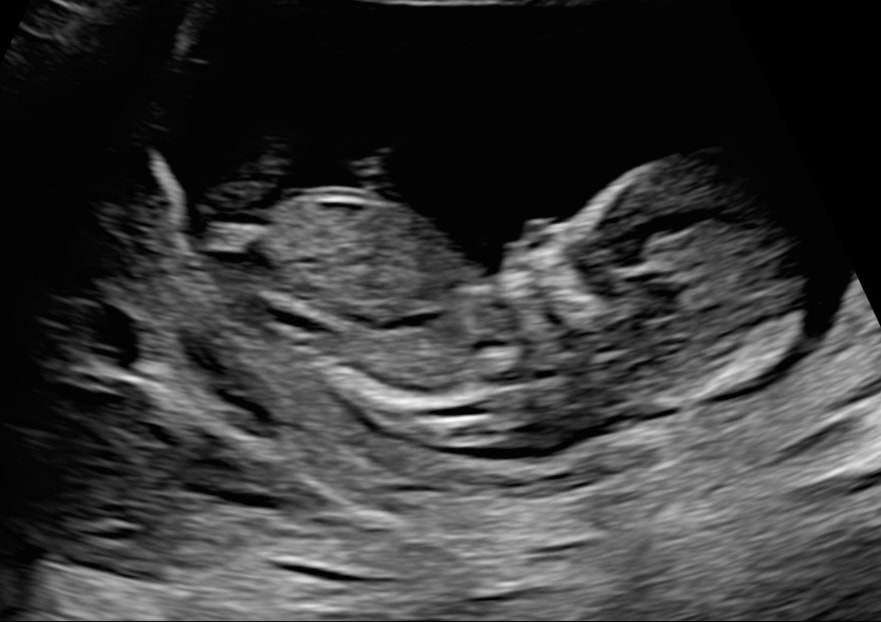

Анализы, скринингиПройден первый скрининг, малыш на УЗИ был невероятно активным — вовсю пинался, что пока, к счастью, совершенно не ощущается )) Кажется, что похож на мужа) Посчитали все пальчики, очень хорошо было видно носик и губы) На данный момент со мной и с малышом все хорошо. Сердце наполняется бесконечной нежностью и надеждой. Пусть так и будет до самой встречи 🤞🏻